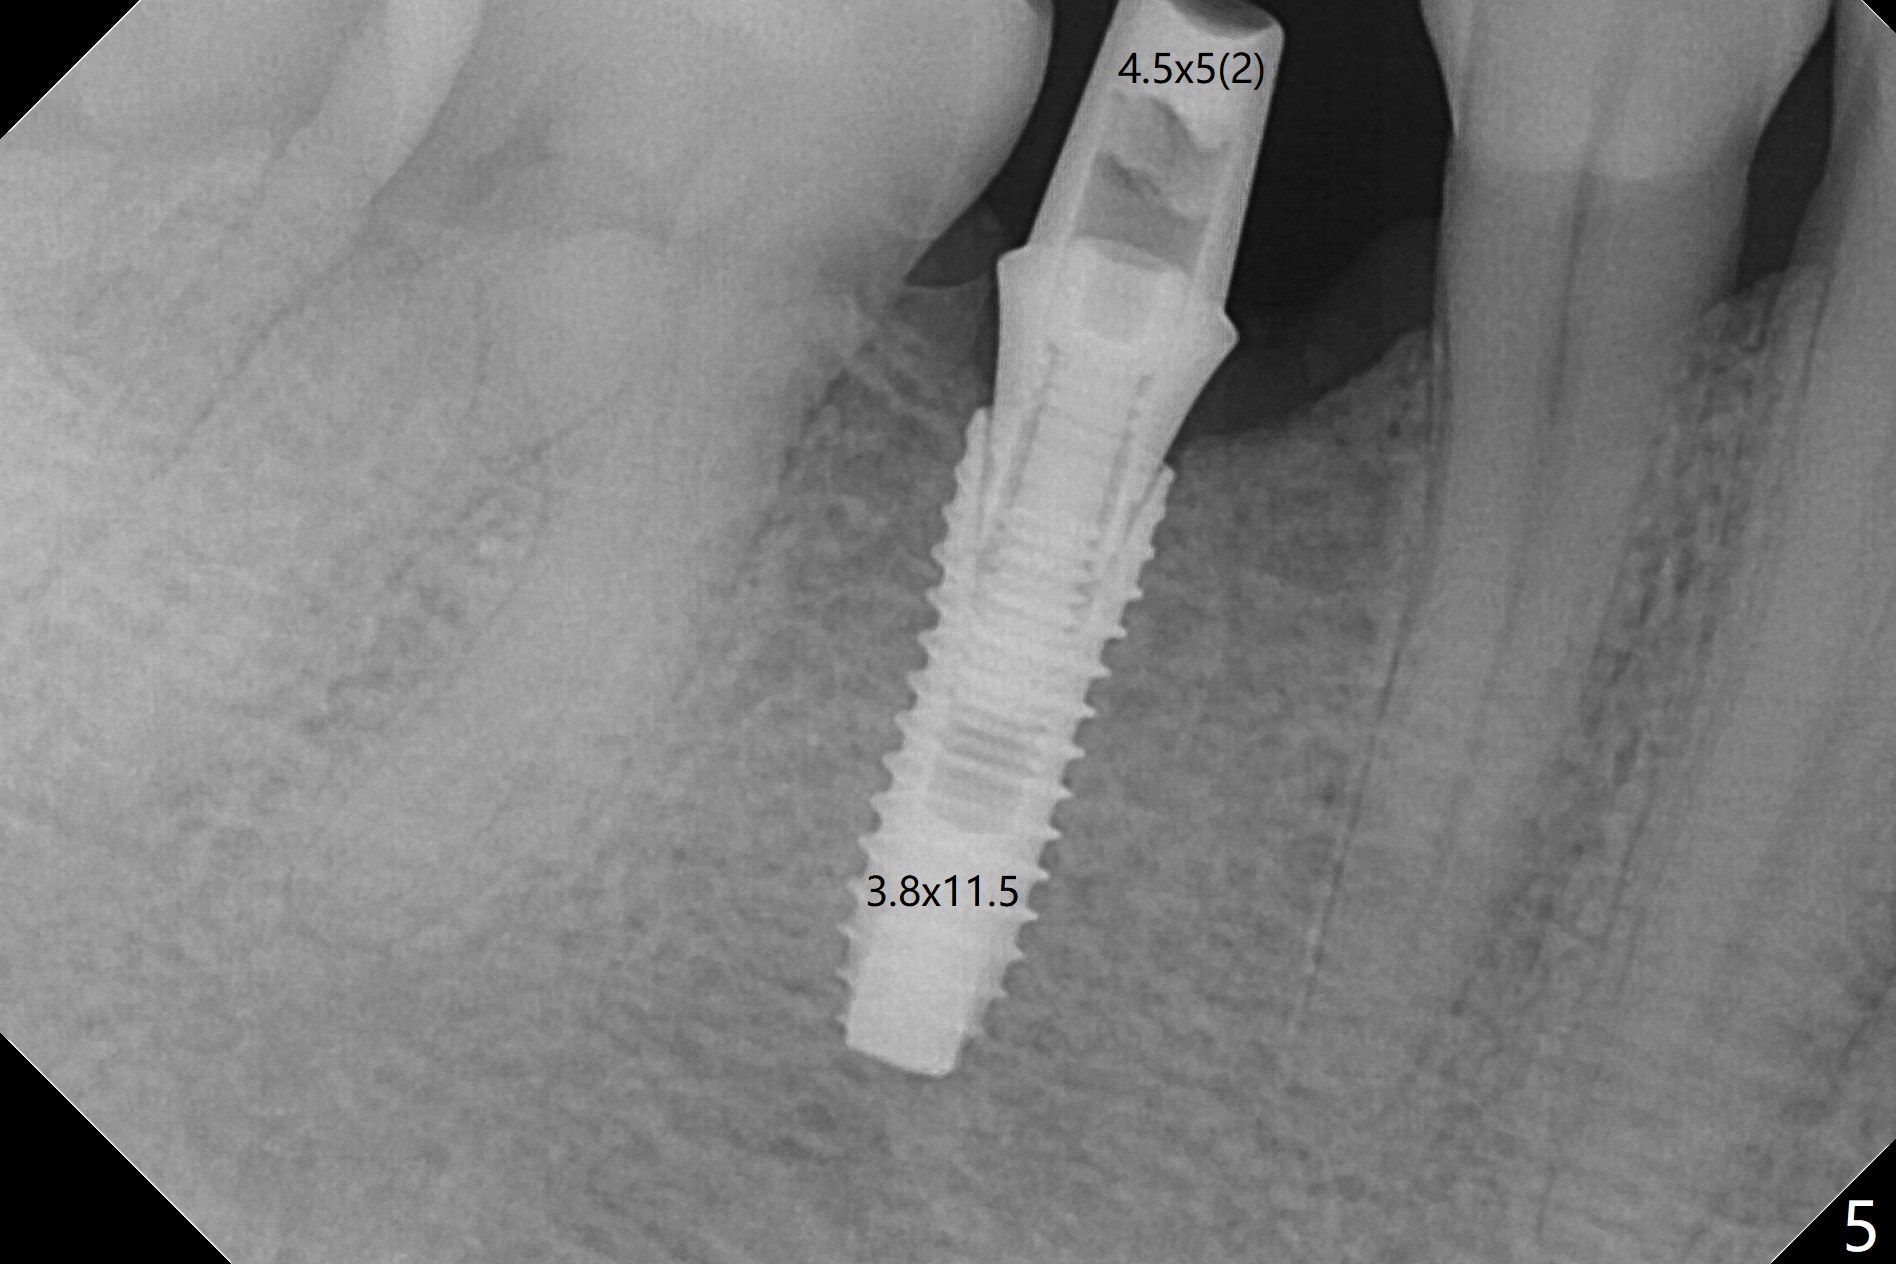

The base of the edentulous ridge at #29 looks wide (Fig.1), but the most coronal portion is the thin soft tissue (Fig.2). It appears that there has been bone resorption since extraction. The initial osteotomy depth is 11.5 mm (Fig.3). Since the Mental Loop seems to be nearby, the depth of subsequent osteotomy (3 mm) remains the same (Fig.4). Although the final depth of osteotomy is 13 mm, the implant placed is short (3.8x11.5 mm, Fig.5,6), as compared to the immediate implant (3.8x18 mm) at the contralateral side (#20). There is mild bone resorption mesially 4 months postop (Fig.7). The crown is loose (poor osteotomy position, guide necessity) 7 months post cementation immediately prior to 18 cementation, although there is no gross bone losss 1 year 7 months post cementation (Fig.8).